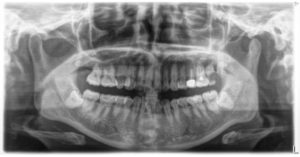

術前の状態です。

左上の前歯(→)が一本だけ黒く変色しています。

このように一本だけ黒くなっているときは、

神経の治療を過去に行なっている、

歯を過去にぶつけた、

といったケースがほとんどです。

この歯は神経を過去に取っているために黒く変色していますが、

それ以前に神経の残りカスのようなものが治療で除去しきれていないのが大きな原因でした。